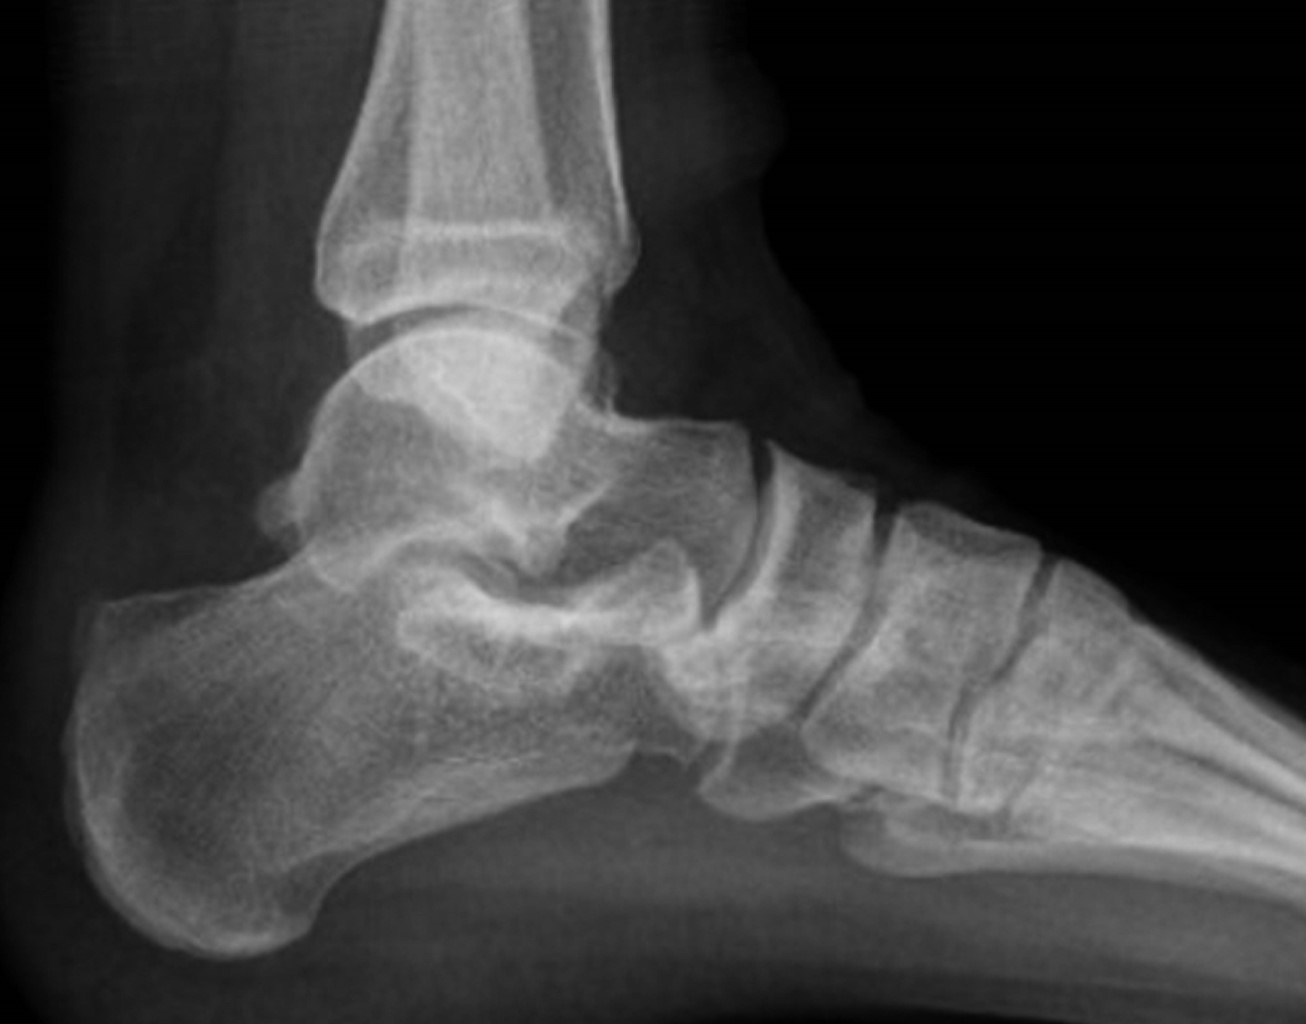

En nuestra primera consulta se envió a terapia física y rehabilitación realizando un total de ocho sesiones dentro de nuestra institución, no mostrando mejoría ni disminución del dolor, por lo que se solicitaron estudios de imagen, los cuales consistieron en radiografía anteroposterior y lateral de tobillo en la cual se evidenció adecuada congruencia de la articulación tibioastragalina y tibioperonea, exostosis posterosuperior de calcáneo de 6 milímetros de altura con relación a la línea articular superior, y alteraciones en la grasa de Kager (Figuras 1 y 2). De igual manera, se realizó resonancia magnética de tobillo evidenciando tendinitis aquílea, bursitis retrocalcánea y líquido en la bursa retroaquílea de aproximadamente 3 cm3. Se observa tendón aquíleo engrosado en su inserción y tendinitis insercional con edema óseo en región posterior de calcáneo (Figura 3).

Figura 3